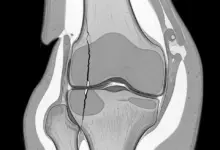

Na prática, a osteotomia ao redor do joelho é indicada com mais frequência para corrigir desalinhamentos, redistribuir carga articular e preservar a articulação em perfis selecionados, sobretudo quando ainda há espaço para adiar procedimentos mais agressivos.

A osteotomia do joelho entra no planejamento quando existe desalinhamento do membro, sobrecarga localizada e quadro compatível com preservação articular.

Em boa parte dos casos, o raciocínio cirúrgico busca mudar o eixo mecânico para reduzir a pressão sobre a área mais sofrida.

Aqui geralmente ocorre uma virada importante. O paciente passa a ganhar mais confiança para apoiar, desde que a evolução clínica e radiográfica autorize esse passo.

Existem protocolos com restrição de apoio por cerca de seis a oito semanas, seguidos de aumento progressivo da carga conforme consolidação e controle clínico.